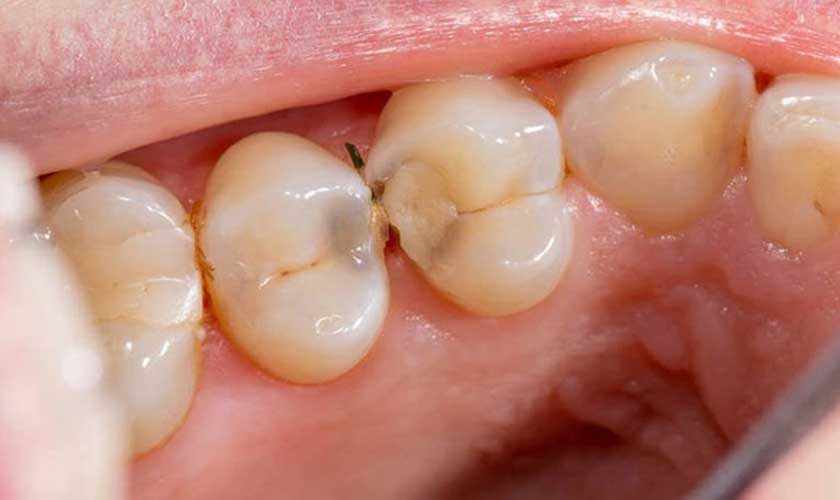

Bột trám răng không thể ngăn chặn vi khuẩn tấn công răng miệng

Tuy nhiên, về mặt lâu dài, bột trám răng tại nhà không thể ngăn cản được vi khuẩn xâm nhập và tổn thương sâu bên trong ngà răng, tủy răng vì phần răng bị sâu đã không được làm sạch khi chúng ta tự trám răng tại nhà.

Hơn nữa, chúng ta chỉ nên dùng bột trám răng nếu chỉ bị sâu răng mới chớm hoặc nứt răng nhẹ. Trong những trường hợp sâu răng gây đau răng, viêm tủy răng hoặc nứt mẻ lớn thì chúng ta cần được kiểm tra và đánh giá tình trạng để có phương pháp điều trị phù hợp, tránh nhiễm trùng nặng dẫn đến những biến chứng như mất răng, áp-xe răng, viêm mô tế bào, nhiễm trùng máu…